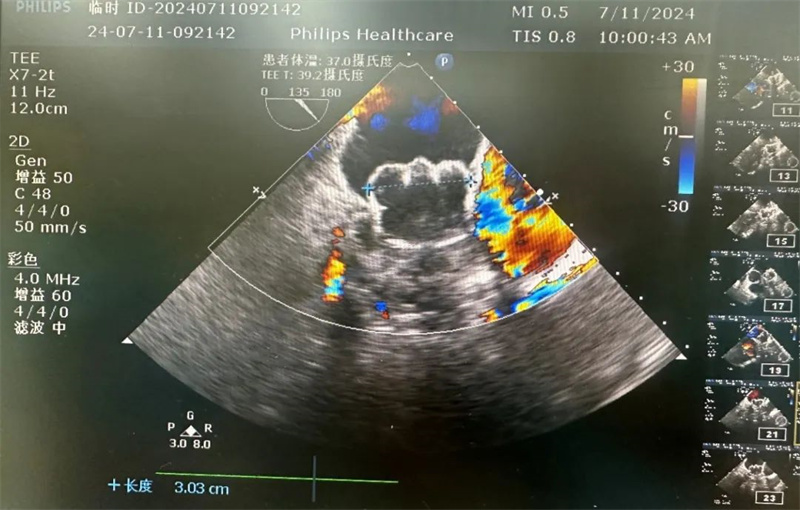

超声显示:封堵器送入后,位置、锚定情况均良好,TEE135°下压缩比为14%,牵拉试验稳定,无残余分流,符合PASS原则,遂完全释放,复查造影提示封堵器封堵完全,最终手术顺利完成。

TEE下评估位置与残余分流

TEE下评估测量压缩比(14%)